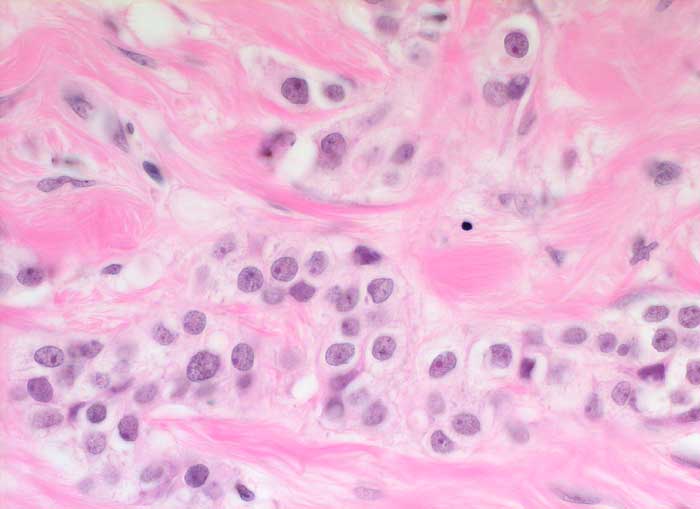

Das invasive Mammakarzinom zeigt zytologisch eine homogene Population maligner Zellen. Typischerweise sollten die Ausstriche zellreich sein und alle vorhandenen Zellen sollten maligne aussehen. Wenn man atypische Zellen suchen muss, ist der Ausstrich nicht diagnostisch für ein Karzinom, kann aber gleichwohl verdächtig sein. Die malignen Zellen sind in lockeren Gruppen gelagert und viele liegen einzeln. Crowding, Zellkannibalismus und Kernmolding sind gute Hinweise auf Malignität. Myoepithelien sind meistens aber nicht immer abwesend. Mammakarzinomzellen sind eher monomorph und deutlich grösser als normale duktale Epithelien. Zellkerne, die grösser sind als zwei Erythrozytendurchmesser, sind tumorverdächtig. Fast immer sind Kerbungen der Zellmembran nachweisbar. Das Chromatin ist im Gegensatz zu anderen Adenokarzinomen fein granulär und gleichmässig im Kern verteilt. Nukleolen sind meist unscheinbar. Makronukleolen sprechen für ein invasives Karzinom.

Die Kohäsivität ist das wichtigste Kriterium zur Feststellung des Differenzierungsgrades. Bei hoch differenzierten Karzinomen finden sich Verbände, bei wenig differenzierten liegen die Tumorzellen vermehrt einzeln. Wenig differenzierte Karzinome zeigen gesteigerte Kernatypien und der Hintergrund ist eher detritisch aufgrund ausgedehnter Tumornekrosen.

Unten werden Beispiele von einem hochdifferenzierten und einem wenig differenzierten Mammakarzinom gezeigt.